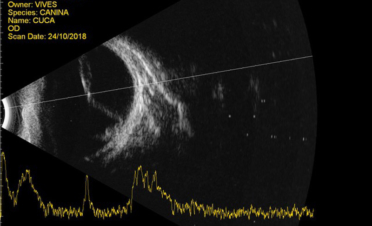

Ecografía bidimensional

Permite visualizar imágenes del globo ocular y la órbita en dos dimensiones.

Se suele utilizar en casos de:

- desprendimiento de retina

- hemorragias en vítreo

- cataratas

- hiperplasias

- medición de lentes intraoculares